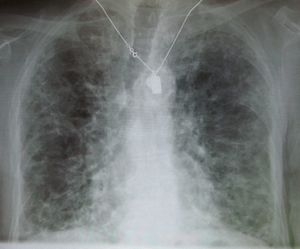

الرئة